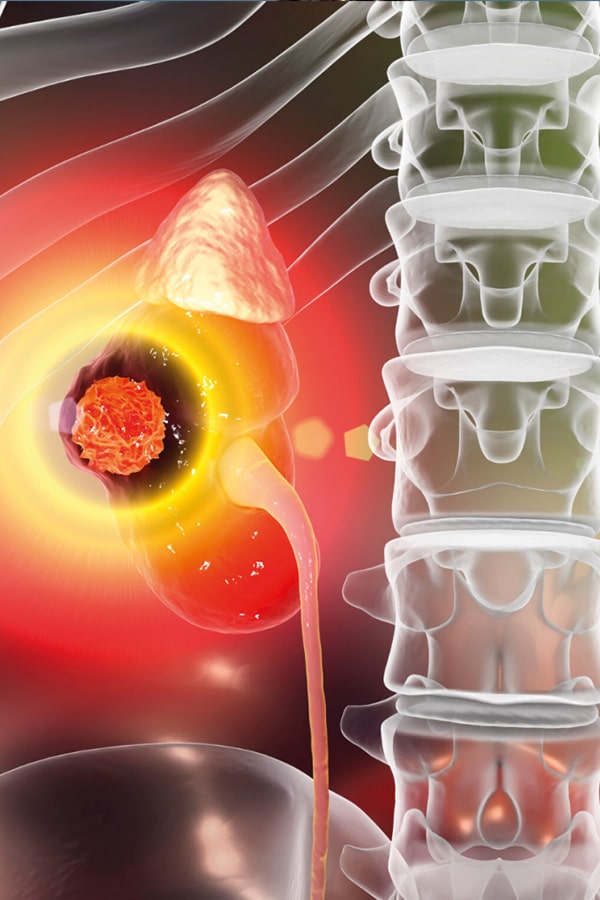

Un tumor renal es una masa anormal de células que se forma en los riñones. Estos tumores pueden ser benignos o malignos y pueden afectar uno o ambos riñones. Por lo general, los tumores renales son asintomáticos en las primeras etapas, lo que hace que sean difíciles de detectar. Sin embargo, a medida que el tumor crece, pueden aparecer síntomas como dolor en el costado, sangre en la orina y pérdida de peso sin explicación.

El tumor renal puede presentar una variedad de síntomas, pero muchos pacientes pueden no sentir ningún síntoma durante las primeras etapas de la enfermedad. A medida que el tumor crece, los síntomas pueden incluir dolor intenso en la parte lateral o posterior del cuerpo, sangre en la orina, fatiga, pérdida de peso no intencional, fiebre, sudores nocturnos y una masa palpable en el abdomen o la parte posterior.

En algunos casos avanzados, los pacientes pueden experimentar hinchazón en el abdomen, venas abultadas cerca del riñón afectado, inflamación en las piernas y disminución de la función renal. Los síntomas pueden variar dependiendo del tipo de tumor renal, su ubicación y la etapa de la enfermedad. Por lo tanto, es importante tener en cuenta cualquier cambio en la salud y programar una evaluación médica inmediata si hay síntomas preocupantes.